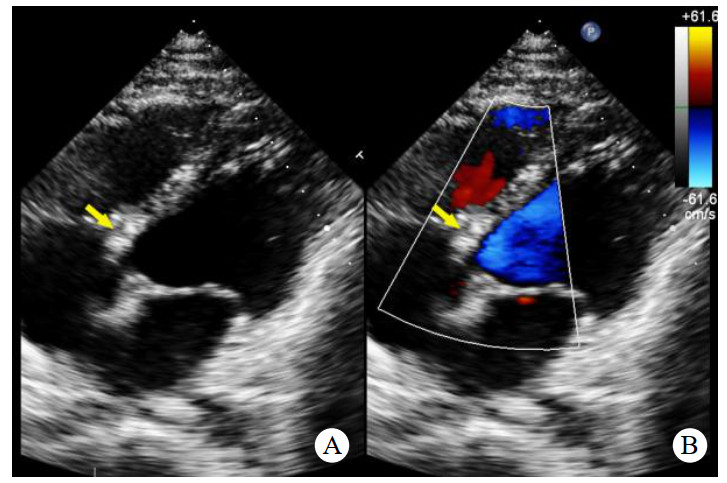

术前心脏计算机断层扫描血管造影(computed tomographyangiography, CTA)检查未能明确诊断右乏氏窦瘤破裂(图 4),这给临床医生带来一定困惑。经急诊超声心动图检查及临床医生全面评估后行右乏氏窦瘤破裂修复术和主动脉瓣成形术。取适当大小的牛心包补片,间断褥式缝合修补破口及室间隔夹层,并行主动脉瓣成形术。术中经食道超声心动图显示窦瘤破裂修补完好,分流消失,主动脉瓣瓣叶开闭良好,反流消失。术后1个月复查,二维超声心动图显示主动脉短轴切面:右乏氏窦瘤破裂修补处回声增强,连续性好;CDFI:该处分流消失。主动脉瓣瓣叶开闭正常。胸骨旁四腔心切面显示如上(图 5),室间隔回声稍不均质,室间隔夹层动脉瘤完全塌陷,未见夹层动脉瘤显示。

| 注:A为2D超声显示胸骨旁四腔心切面右乏氏窦瘤破裂修补处(黄色箭头)回声增强,连续性好;B为CDFI显示该处分流消失 图 5 2D及CDFI显示右乏氏窦瘤破裂修复术和主动脉瓣成形术后表现 |